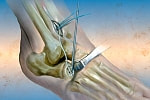

●内視鏡下の切除術が主流

滑膜切除術は、かつては関節を大きく切り開いて滑脱をとり除く外科的切除術が行われていましたが、現在は内視鏡下での手術が主流になっています。

皮膚に小さな孔をあけ、内視鏡(関節鏡)を挿入して、モニターに映し出された画像を見ながら行う手術です。切開する部分が小さいため、患者さんへの負担も少なく、回復が早いというメリットがあります。